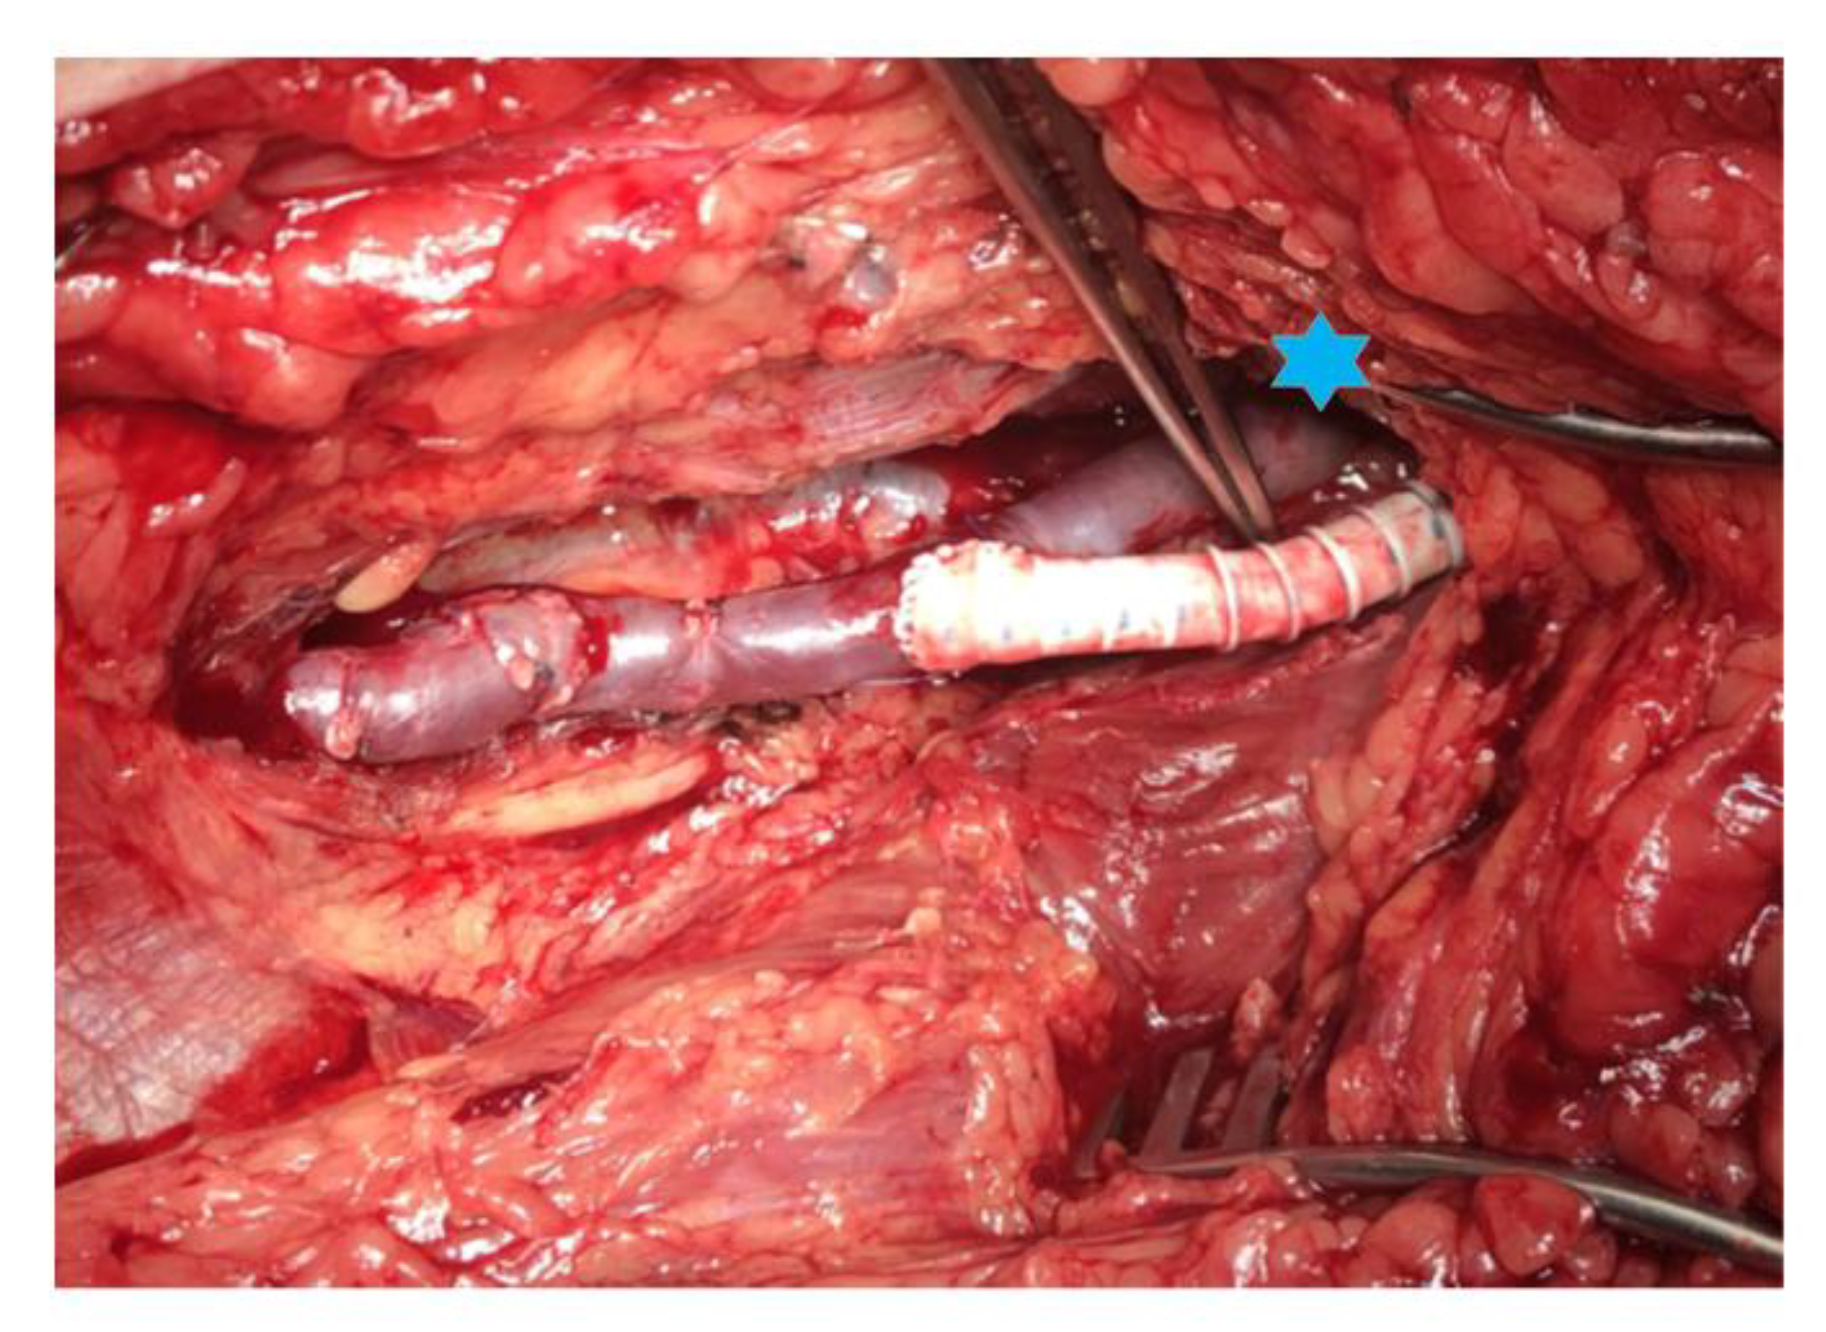

3.2. Bypass Configuration